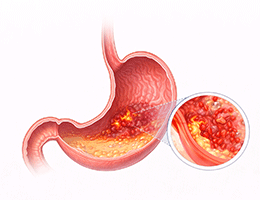

위염 (Gastritis)

소화불량 (Dyspepsia)

기능성소화불량 (Functional Dyspepsia)

헬리코박터 감염 (Helicobacter pylori Infection)